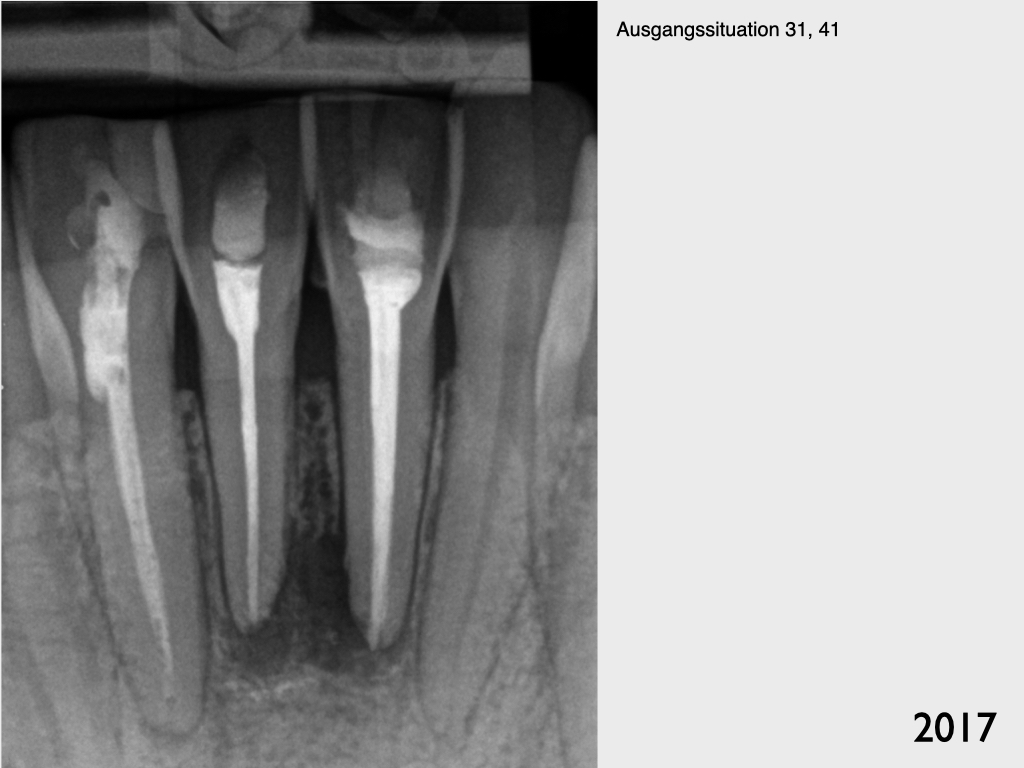

Frontzahntrauma